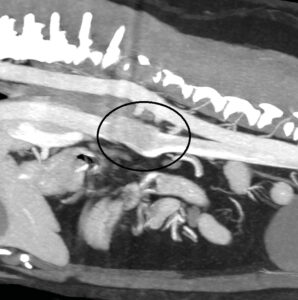

La tomografía computarizada (TC) es una técnica que va a emplearse habitualmente de forma previa a la cirugía en masas adrenales caninas, debido a que se considera más precisa que la ecografía para la detección de invasión vascular: tiene una sensibilidad y especificidad aproximada del 90 %28,29 (imagen 5) y esto es de gran importancia ya que, si existe invasión vascular, el abordaje quirúrgico será diferente.

Imagen 5. Imágenes de TC en ventana de tejidos blandos en fase venosa tras la administración de contraste reconstruidas en planos sagital (A) y dorsal (B) donde se observa un defecto de llenado de la vena cava caudal (círculo negro) por la presencia de una masa hipoatenuante de 4 cm de longitud que se corresponde con un tromoboembolismo tumoral a través de la vena frénico abdominal (*) por un feocromocitoma en la glándula adrenal izquierda (M).

Además, la presencia, el tamaño y la extensión del trombo van a tener un impacto sobre el pronóstico29. Recientemente se ha descrito un sistema de clasificación que puede ser de ayuda para determinar si existe o no invasión vascular, ya que en ocasiones puede resultar complicado porque, debido al gran tamaño de las masas, puede producirse una compresión vascular que dificulta la exploración29.